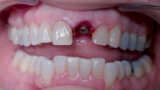

Fig. 2: Initial situation, intra-oral view.